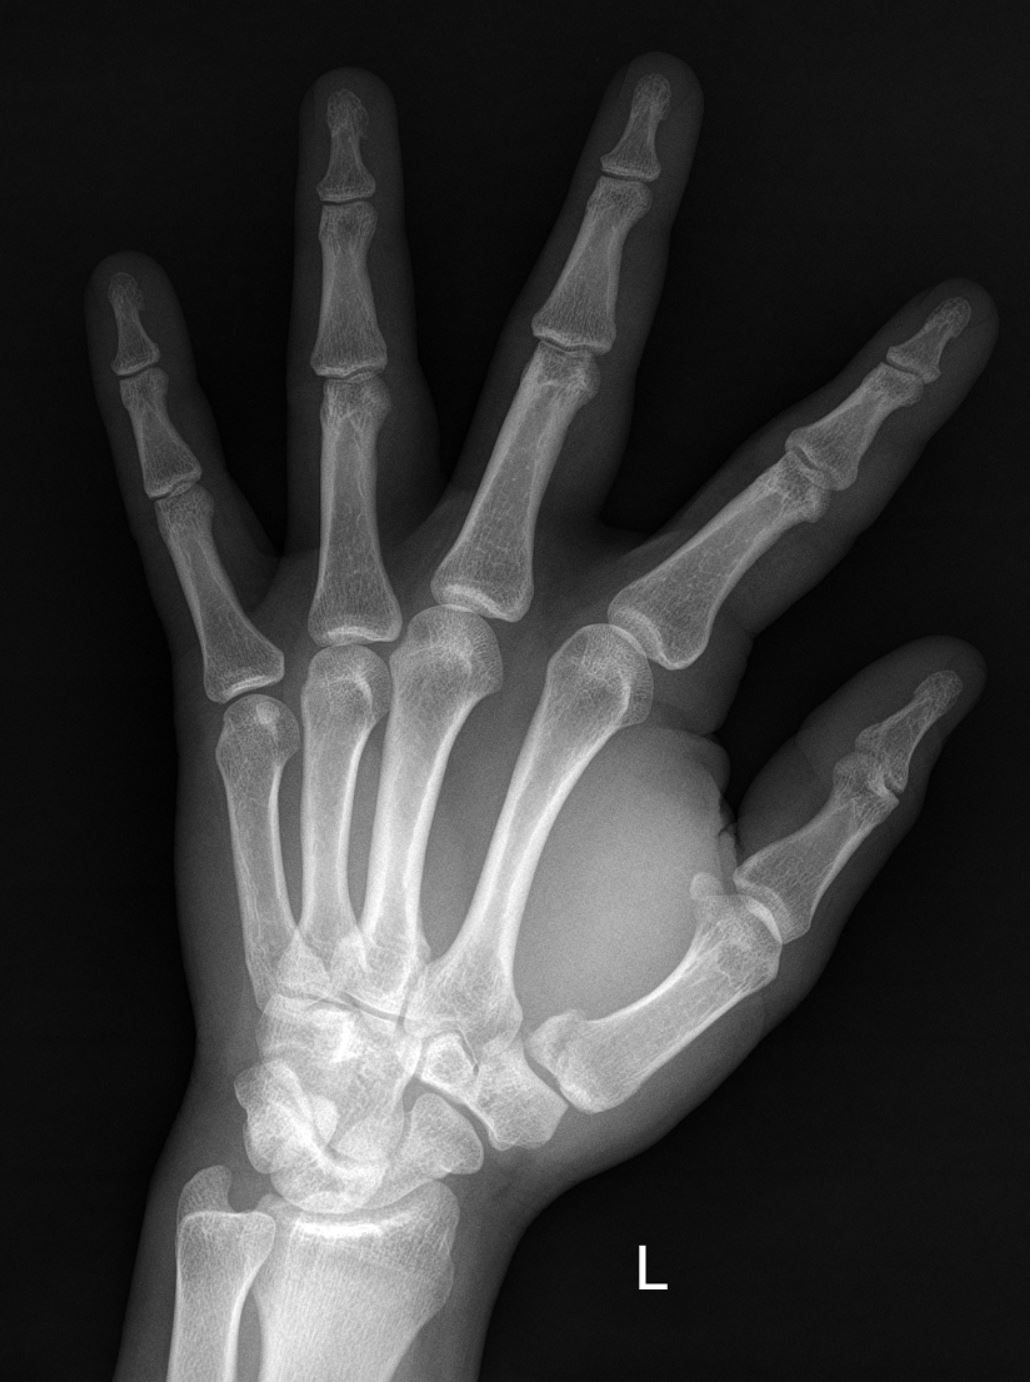

Sie haben folgende Anamnese in Ihrer Anforderung: Z.n. Sturz auf die linke Hand. Welche Verletzung erkennen Sie auf vorliegendem Röntgenbild?